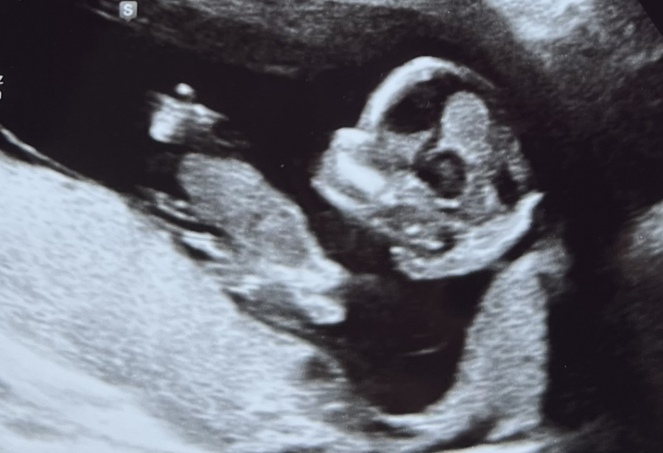

Ultraschall - auf keinen Fall? - Tagebücher aus der Schwangerschaft von Jenny aus Hamburg